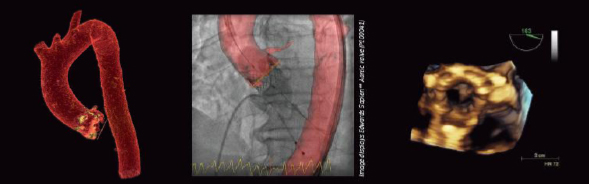

高度なTAVI を治療計画策定時から的確に支援するDiscovery IGS 730

左: Valve Planning による治療計画の描出

中央: Heart Vision を使用した手技中のガイド

右: 超音波によるデバイスの位置確認